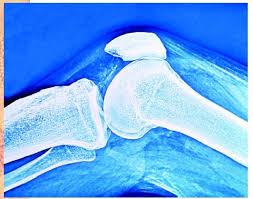

High levels of uric acid form small crystals in joints and tissues, causing pain and swelling – the main symptoms of the condition once known as the 'disease of kings'. Gout is the most common form of inflammatory arthritis, affecting up to two per cent of the world's population. Understanding how these common genetic variants increase uric acid levels in the blood may lead to improvements in the treatment and prevention of the disease. It could also help research into urate-lowering drugs.